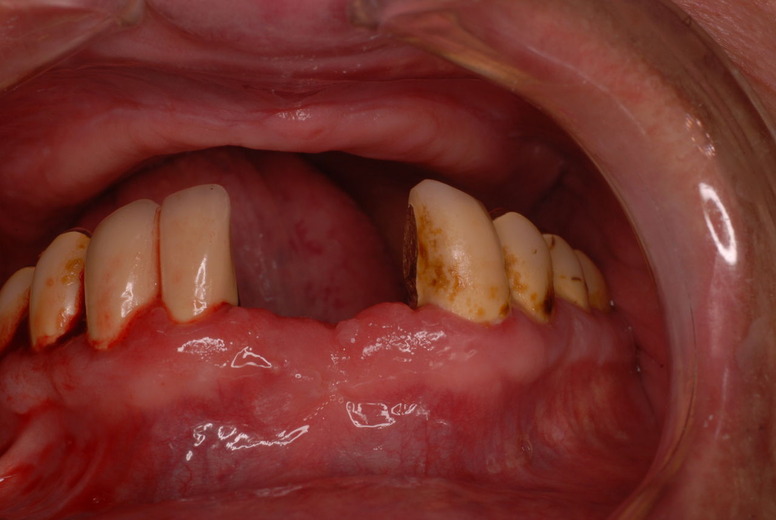

flabby gumと言いまして、骨が溶けてぶよぶよになった歯茎が残るとても入れ歯が吸着したり安定的に食べ物が噛めるような状態でないのです。(歯周病で骨が溶けたとか合わない入れ歯を入れているとなりやすい。)

そしてその部分が擦れて痛む為食事もできないのです。それ以上に驚いたのは、歯を磨いたり歯周病の治療の話を聞いたことがないという事実です。

触るとぶよぶよしていて強く押すと痛みがあります。

殆ど出っ張りがない上顎の部分です。